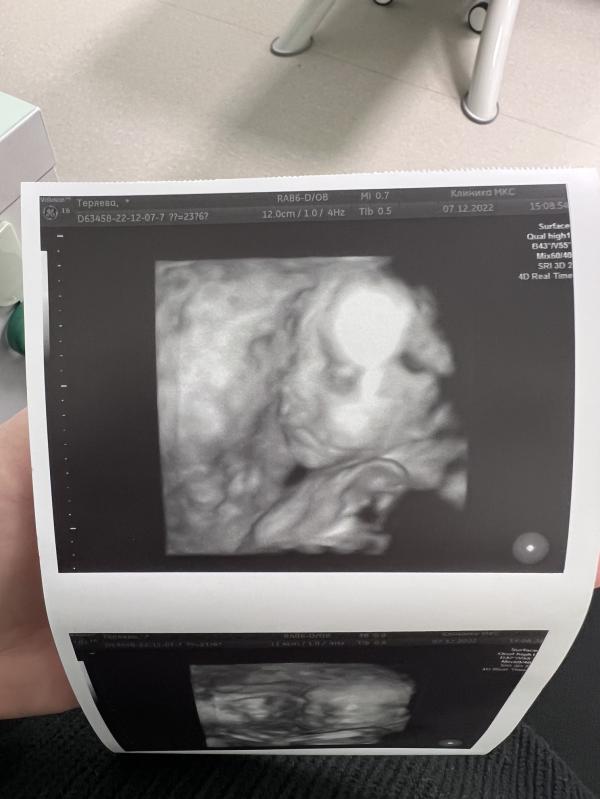

Наш сладкий пирожочек ☺️

Такой уже человек, даже похожие черты вижу от мужа и от себя 🫶